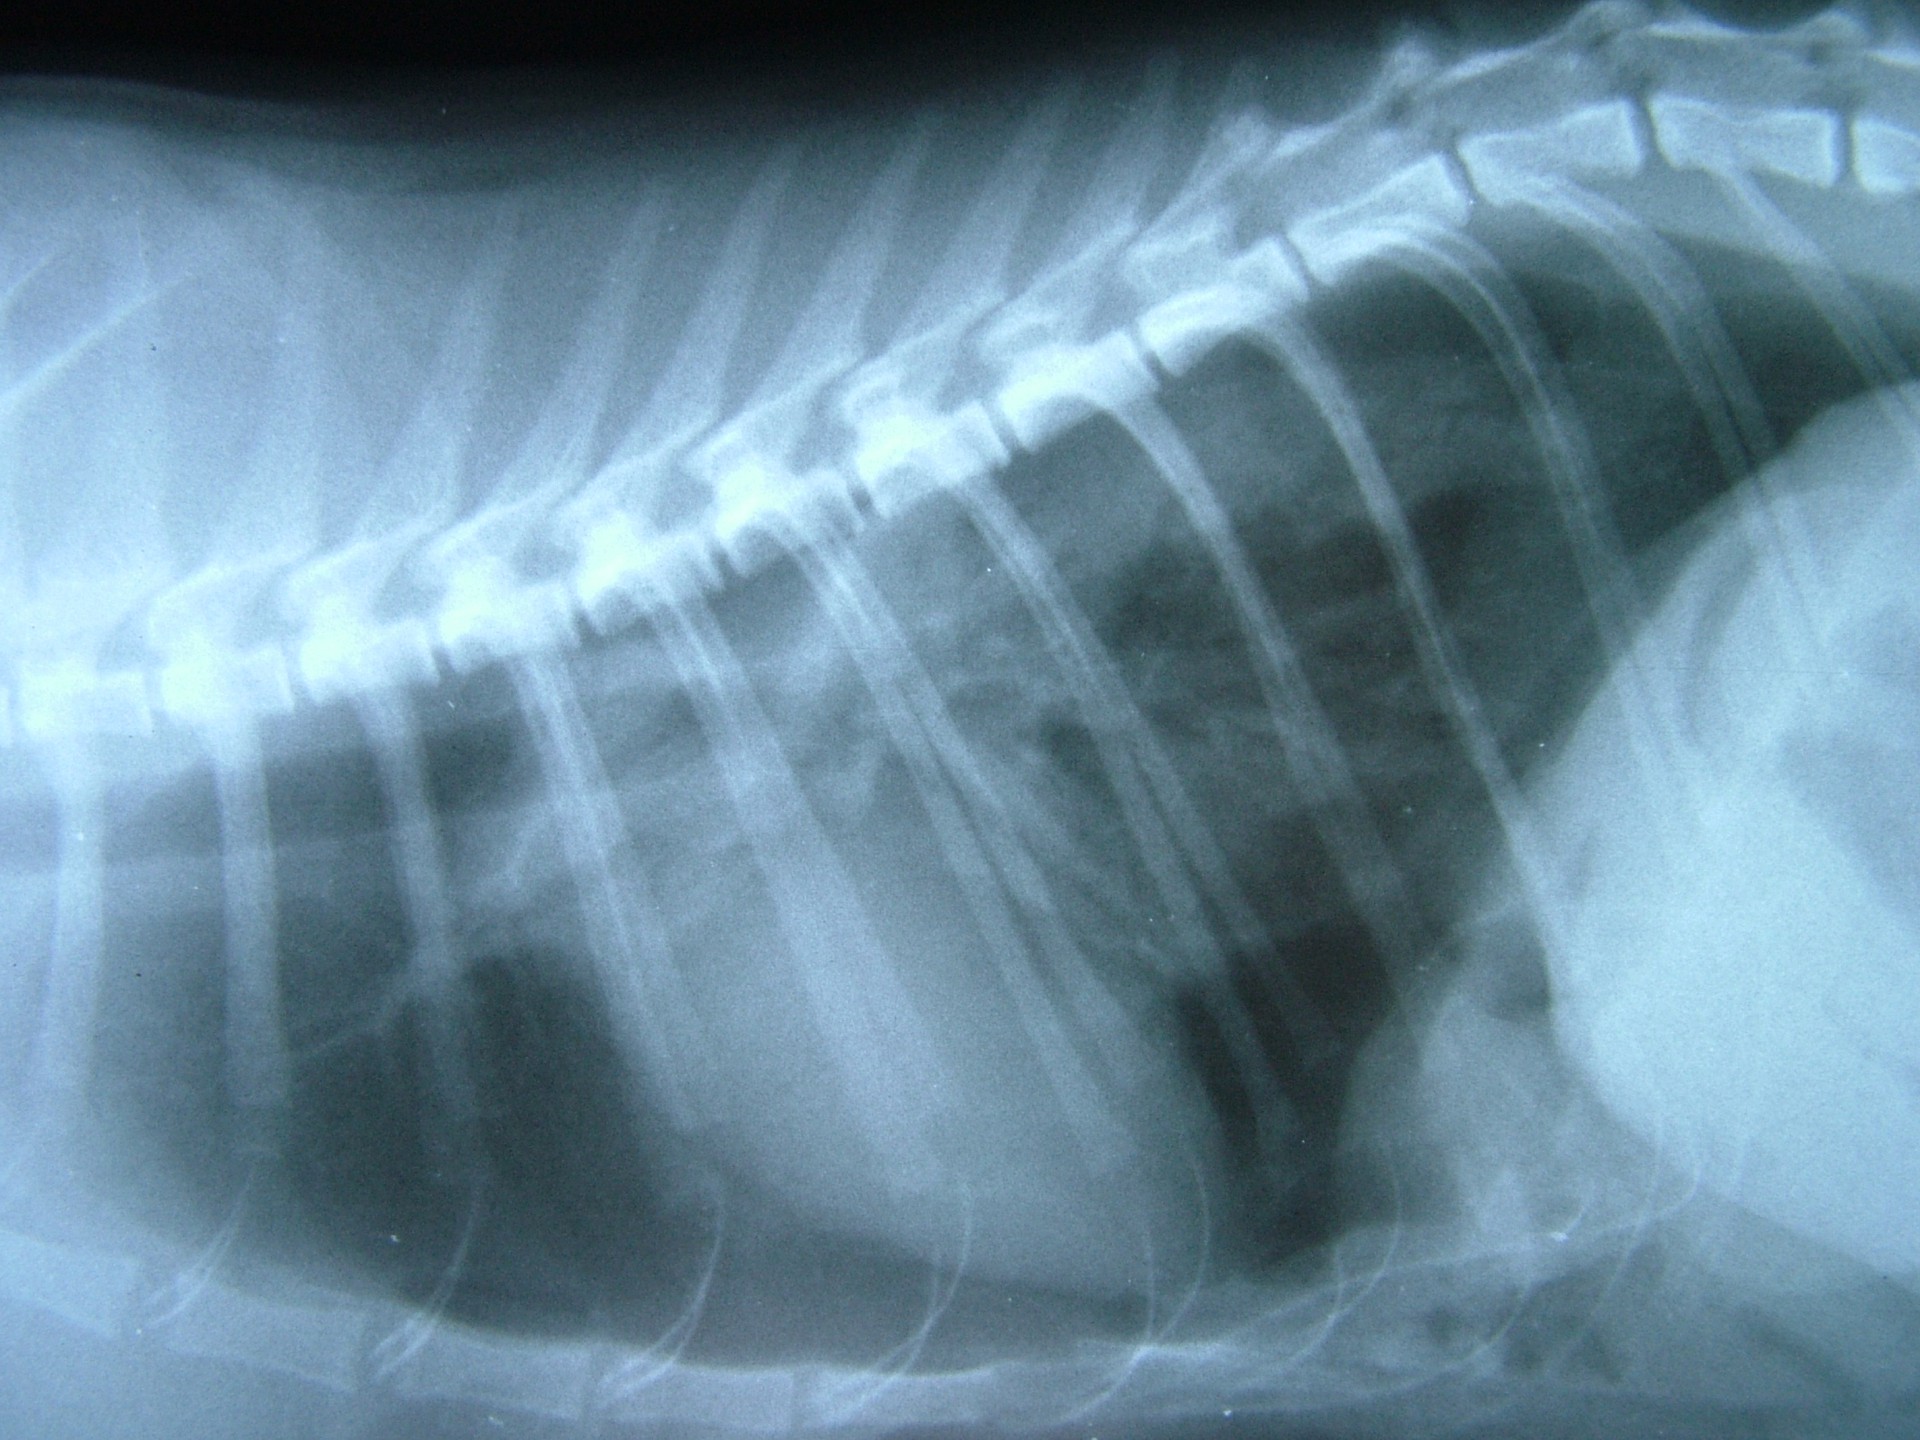

Mindhárom rekeszsérv forma meglehetősen ritkán fordul elő. A diagnózis felállítása a kórelőzmény, a klinikai tünetek a mellkas röntgenvizsgálata, a hasüreg ultrahangos vizsgálata alapján lehetséges.A rekeszsérv műtéti ellátása során a legnagyobb kihívást az jelenti, hogy a hasüreg megnyitását követően a sérvkapun keresztül levegő kerül a mellüregbe, ezáltal az állat spontán légzése leáll, így a műtét teljes ideje alatt asszisztált lélegeztetésre van szüksége.A műtét során a mellkasba előesett szerveket reponáljuk, a rekesz folytonosság hiányát megszüntetjük és a mellkasban lévő szabad levegőt eltávolítjuk, ezzel biztosítva az állat spontán légzését. A műtétet követő napokban legfontosabb feladat a vérkeringés és a légzés folyamatos, kórházi körülmények közötti kontrolálása.Az idejében felismert és megfelelően ellátott veleszületett rekeszsérv jó eséllyel gyógyítható, a traumás eredetű sérv ellátásának eredményességét általában az egyéb szervek sérülése határozza meg.